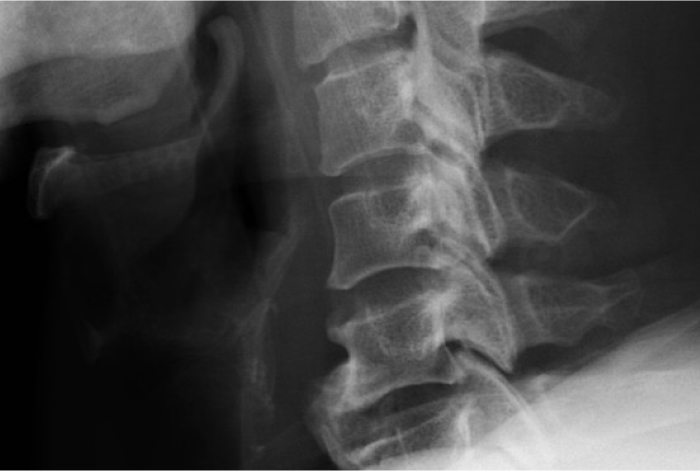

목을 젖히면 팔이나 다리가 아프고 저리시나요?

원인 모를 보행 불안정, 손기능 저하가 점점 심해지시나요?

척추 뼈 안쪽의 인대(후종인대)가 딱딱하게 뼈처럼 굳어지는 질환입니다.

척수가 눌려 신경 손상, 사지마비, 보행 장애 등으로 진행될 수 있습니다.